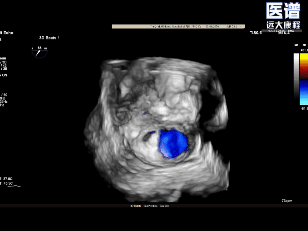

TEE-3D

TEE-3D血流

释放后3D评估(组织桥稳定)

释放后3D评估(反流少量)